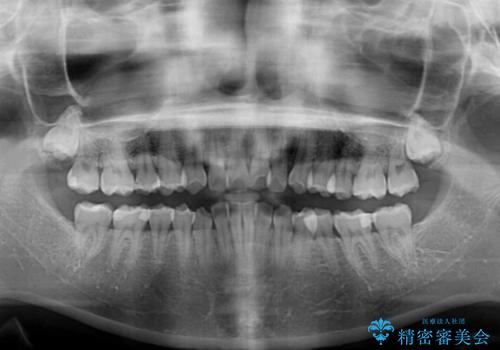

- デコボコを気にして来院された患者様です。

インビザラインでもワイヤー装置でも対応可能でしたが、自己管理の煩わしさの観点から、楽して治療のできるワイヤー装置を選択されました。

抜歯するほどではないものの、やや口元の突出感が気になっていたので、補助装置により上顎臼歯を後方に移動させることで、突出感改善を図ることとしました。

1年弱の短期間で、望み通りのスッキリとした口元に仕上げることができました。